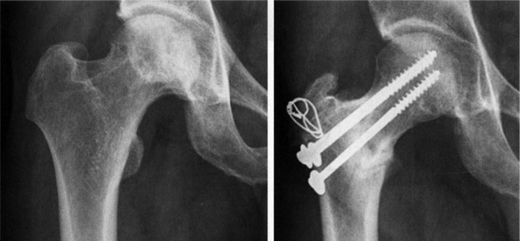

비구 절골술은 여러 방법이 시행되고 있으며 크게 재형성 절골술(Reconstructive osteotomy)과 구제 절골술(Salvage osteotomy) 두 가지로 구분합니다. 재형성 절골술은 비구의 방향을 바꾸어 주어 대퇴골두와의 접촉면적을 넓혀주고 관절에 가해지는 하중을 감소시켜주는 방법으로 퇴행성 관절염을 예방하기 위한 방법입니다

고관절 주위 절골술 이미지